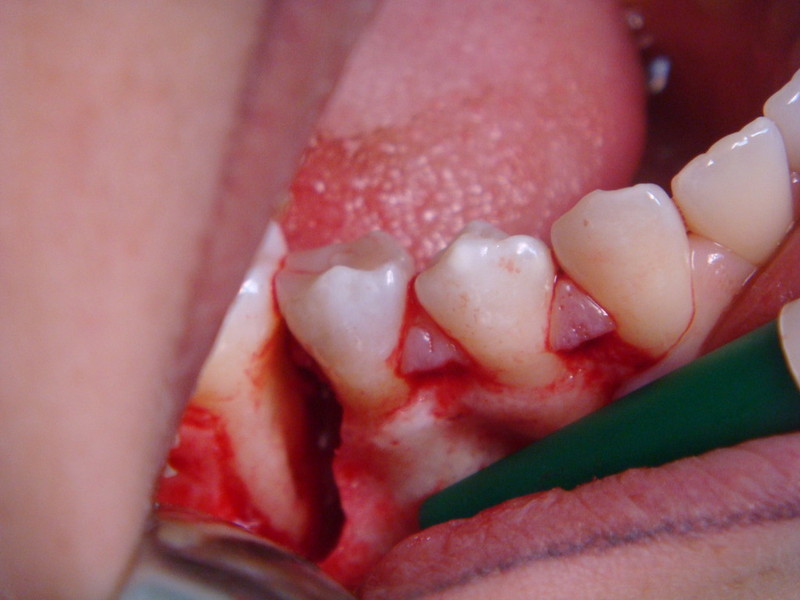

Rigenerazione Gravi difetti parodontali

Rigenerazione difetto parodontale di un canino inferiore con materiale eterologo

rigenerazione grave difetto parodontale a carico del 46

rigenerazione grave difetto parodontale a carico una intera emiarcata